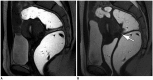

Magnetic resonance imaging is the optimal modality for pelvic imaging. It is based on T2-weighted magnetic resonance (MR) sequences allowing uterine and vaginal cavity assessment as well as rectal evaluation. Anatomical depiction of these structures may benefit from distension, and conditions either developing inside the lumen of cavities or coming from the outside may then be better delineated and localized. The need for distension, either rectal or vaginal, and the way to conduct it are matters of debate, depending on indication for which the MR examination is being conducted. In this review, we discuss advantages and potential drawbacks of this technique, based on literature and our experience, in the evaluation of various gynecological and rectal diseases.